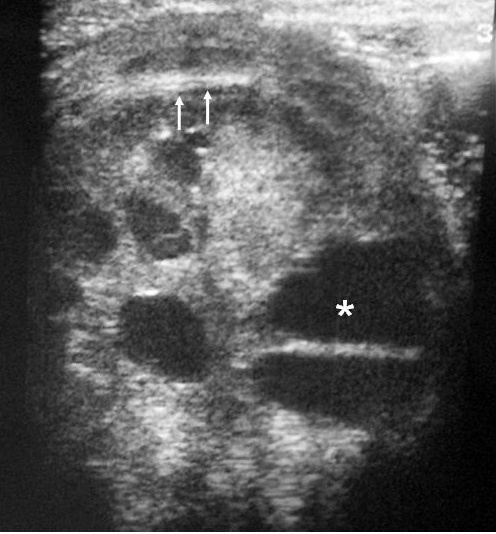

De los 11 nefromas mesoblásticos (con edad y presentación mostrados en la tabla 1) en 7 pacientes el tumor fue sólido y en 4 quístico, con presencia de un polo sólido. En 5 pacientes se encontraron áreas compatibles con necrosis, en dos sangrado intracavitario y en uno función excretora dentro de la masa. Siete pacientes tenían una colección subcapsular y 5 un anillo ecogénico periférico en la ecografía (figs. 1 y 2).

Fig. 1. Nefroma mesoblástico. Niño de 5 meses con masa abdominal palpable. (A) Ecografía abdominal, corte renal izquierdo. Masa en riñón izquierdo predominantemente sólida, con áreas de necrosis (*) y anillo ecogénico en la periferia (flechas). (B) Tomografía computarizada abdominal con contraste intravenoso. Corte al nivel del tercio medio del riñón. Masa en riñón izquierdo que cruza la línea media. Áreas de sangrado (S). Parénquima residual conservado en la periferia posterolateral de la masa (flechas).

Los estudios de imagen muestran una masa por lo general de gran tamaño, sólida, que suele englobar el seno renal y puede contener, aunque no es frecuente, áreas quísticas, hemorrágicas y necróticas. No presenta buena delimitación con el parénquima sano y puede existir infiltración local de tejidos vecinos1. En uno de nuestros pacientes, estudiado por masa abdominal y cuadro clínico de obstrucción intestinal, se identificó una masa renal que infiltraba el colon, el bazo y la glándula suprarrenal. Un signo ecográfico característico es la imagen en anillos concéntricos hiper e hipoecoicos en la periferia del tumor5,7. En nuestra serie la ecografía demostró una colección hipoecoica subcapsular en 7 pacientes y anillo ecogénico periférico en 5.